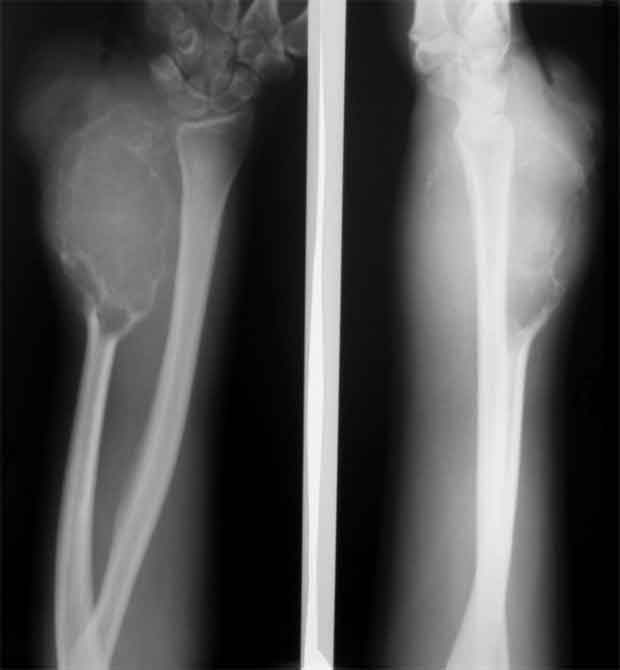

Уважаемые коллеги, госпитализировали, наконец, эту пациентку, чему не очень рады, как клиническая, так и рентгенологическая картины изменились, кроме того Hb 76.Направил на повторную консультацию к онкологу. Остеобластеокластома может себя так вести?

Клинико-рентгенологически очень похоже на хондросаркому..... Хотя, конечно же, необходимо гистологическое заключение...

Плоховато она выглядит на снимках.

Уважаемые коллеги. По данным рентгенограммы опухоль больше похожа на злокачественную фиброзную гистиоцитому или телеангиоэктотический вариант остеогенной саркомы с поражением кожных покровов. По данным 6 отделения ЦИТО (Бурдыгин В.Н., А.В. Балберкин) и докторской диссертации А.Н. Махсона при поражении низкодифференцированной, т.е. высокозлокачественной опухолью кожных покровов или магистральных сосудисто-нервных структур органосохраняющие оперативные методы лечения не показаны, т.к. имеются отдаленные не диагностируемые метастазы. Показано комбинированное оперативное лечение по принципам неоадъювантной ПХТ.

Может при озлокачествлении (литическая форма), но уж больно похоже на хондро SA.